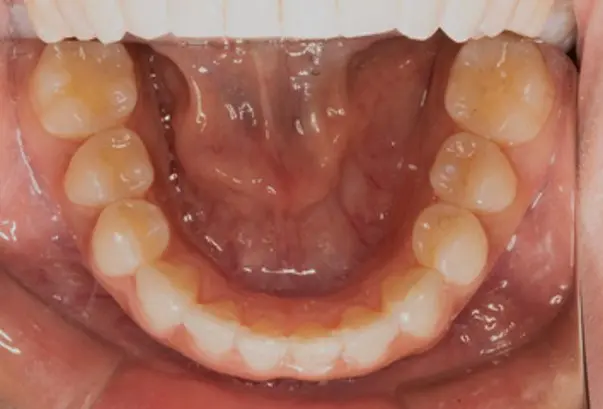

Crowding

Before

After